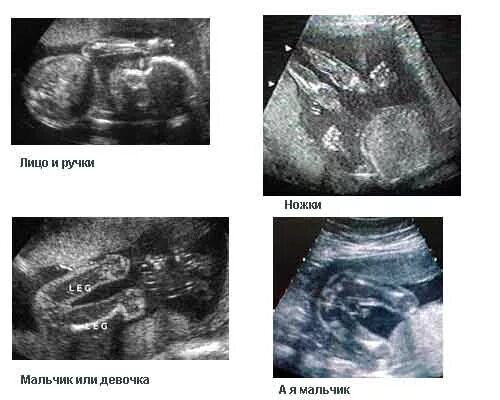

Может врач ошибиться с полом ребенка